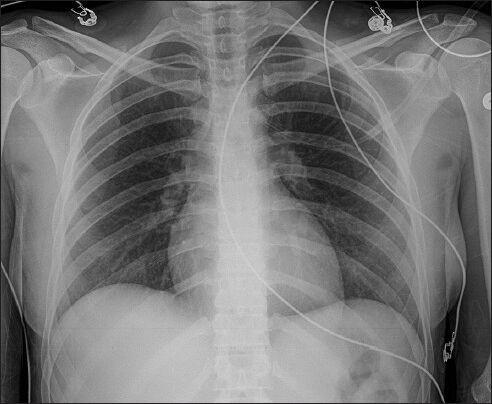

Panic attack: An unusual cause of spontaneous pneumomediastinum.

Int J Crit Illn Inj Sci. 2014 Jan;4(1):91-2. doi: 10.4103/2229-5151.128023.

https://cdn.ncbi.nlm.nih.gov/pmc/blobs/1265/3982377/150621d51006/IJCIIS-4-91-g002.jpg

https://cdn.ncbi.nlm.nih.gov/pmc/blobs/1265/3982377/d292e058871b/IJCIIS-4-91-g001.jpg